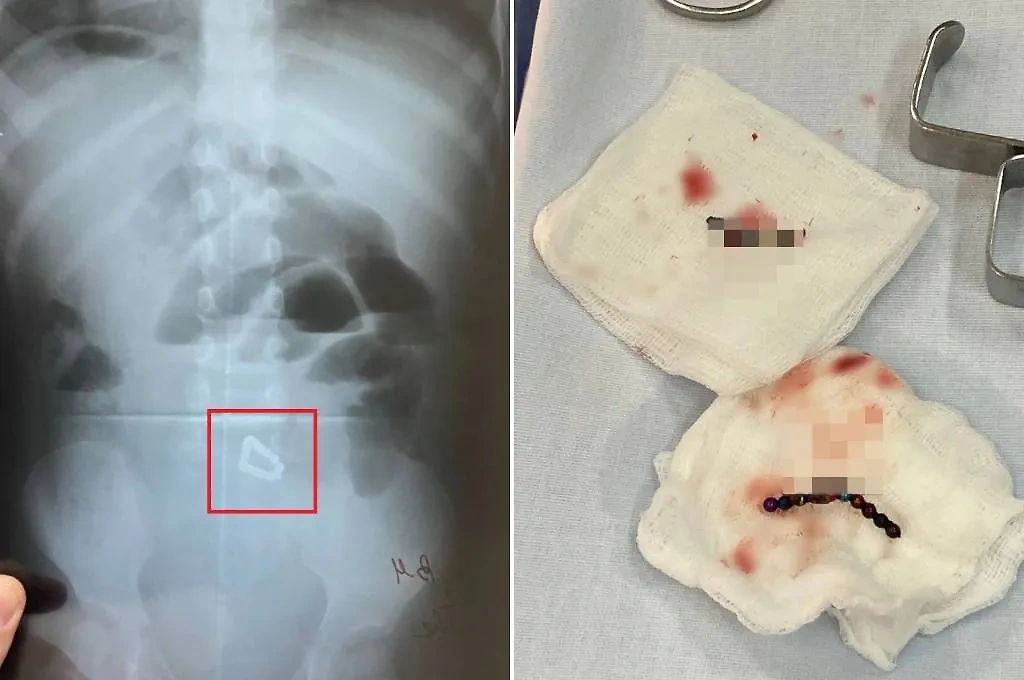

Извлечённые из тела двухлетней девочки магнитные шарики. Фото © VK / Минздрав Республики Башкортостан

«Девочка поступила в КБСМП с жалобами на вялость и многократную рвоту. Сделав рентген-снимок, медики обнаружили в кишечнике ребёнка 17 магнитных шариков от детского конструктора по 2 мм в диаметре», — говорится в сообщении.

В течение двух часов хирурги извлекали инородные тела из кишечника пострадавшей малышки. Всего было зашито три отверстия, проделанных магнитами. На данный момент за состоянием ребёнка ведётся наблюдение, скоро девочку выпишут, подытожили в ведомстве.